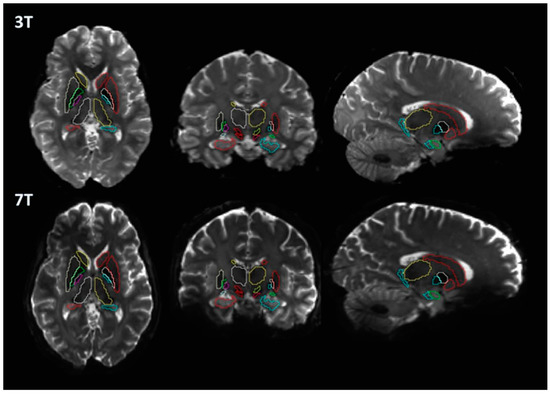

2.3. Image Processing

3. Results